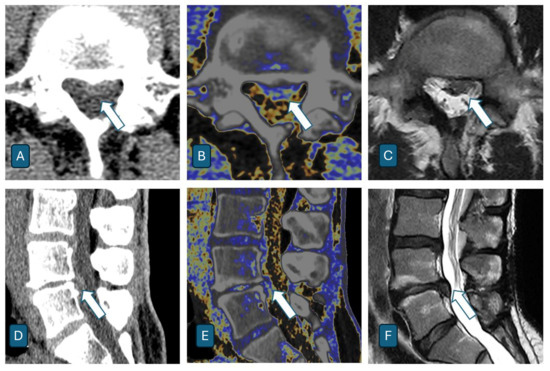

Assessment of Intervertebral Lumbar Disk Herniation: Accuracy of Dual-Energy CT Compared to MRI

- Booz, C.; Nöske, J.; Martin, S.S.; Albrecht, M.H.; Yel, I.; Lenga, L.; Gruber-Rouh, T.; Eichler, K.; D’Angelo, T.; Vogl, T.J.; et al. Virtual Noncalcium Dual-Energy CT: Detection of Lumbar Disk Herniation in Comparison with Standard Gray-scale CT. Radiology 2019, 290, 446–455. [Google Scholar] [CrossRef] [PubMed]